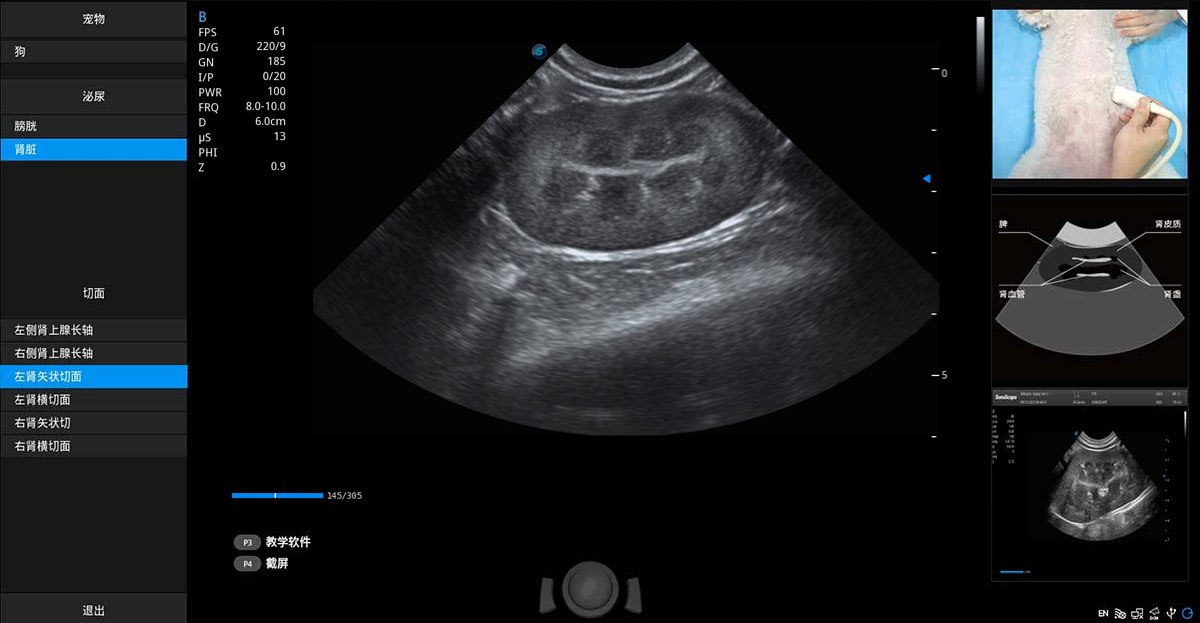

提供解剖示意圖、標(biāo)準(zhǔn)超聲圖像、掃查手法涂和操作者實(shí)時(shí)檢查圖像,指導(dǎo)操作者進(jìn)行標(biāo)準(zhǔn)切面的正確掃查。